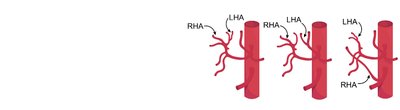

Anatomical Variation: Common in blood vessels, organs, and other structures.

Example: There are multiple common variants in the branching of blood vessels to the liver and gallbladder.